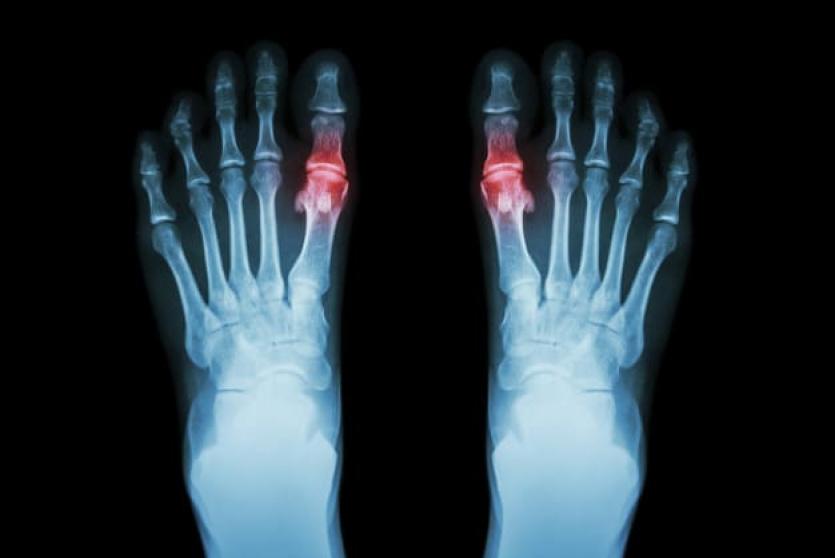

داء الملوك (Gout) أو ما يعرف بالنقرس، هو أحد أنواع التهاب المفاصل (Arthritis) الشائعة الحدوث، الذي عادةً ما يحدث فجأةً في أصبع القدم الكبير مسببًا الام شديدة، من الممكن أن يصيب داء الملوك مفاصل أخرى و يؤثر في المناطق المحيطة بها، مثل الكاحل، الركبة، والقدم.

- الالتهاب والاحمرار: حيث تصبح المفاصل المصابة متورمة، حساسة، دافئة، ومحمرة.

- التصوير بالأشعة السينية.